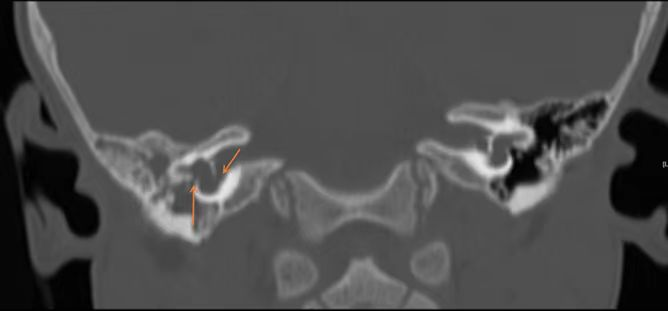

据北京清华长庚医院耳鼻咽喉头颈外科副主任伊海金介绍,脑脊液耳漏是指脑脊液在颅内外压力梯度的作用下,从硬脑膜缺口及其所覆盖的颅骨缺损处经鼻腔、外耳道或开放伤口漏出的现象。这种“鼻涕”和普通鼻涕还不太一样,不粘稠,无色,更像清水。检查显示,患儿系患有先天性内耳结构发育异常,不仅几乎无听力,言语发育受到影响,而且畸形的内耳与颅底相通,导致脑脊液自颅脑流入内耳、中耳、咽鼓管流到鼻腔,造成反复的鼻腔水样涕,过程中还导致感染,引发了脑膜炎、吸入性肺炎等严重疾病。

图片3.png